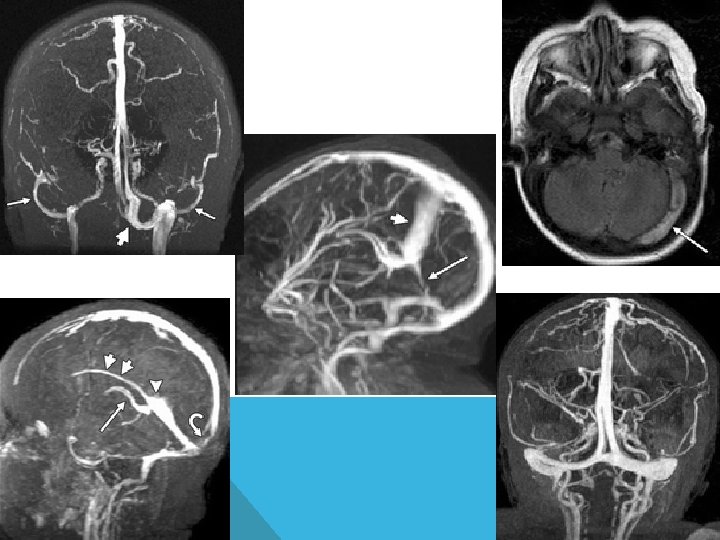

ЦЕРЕБРАЛЬНЫЙ ВЕНОЗНЫЙ ТРОМБОЗ СИНУС-ТРОМБОЗ И ТРОМБОЗ ВЕН

ЦЕРЕБРАЛЬНЫЕ ВЕНОЗНЫЕ СИНУСЫ -верхний сагиттальный -нижний сагиттальный -прямой -латеральные (сигмовидные +поперечные) -каменистые (верхние+нижние) -сфенопариетальные -кавернозные

ЭТИОЛОГИЯ (ФАКТОРЫ РИСКА) 1. Врожденные протромботические состояния: возраст до 6 месяцев, дефицит факторов антисвертывания, внутриутробная гипоксия, внутриутробная инфекция, пороки сердца, арахноидальные кисты, порэнцефалия. 2. Приобретенные: инфекция местнаяпроникающее ранение, абсцесс, эмпиема, менингит, отит, тонзиллит, синусит, стоматит, дерматит общая- бак. септицемия, эндокардит, тиф, туберкулез, вирус (корь, гепатит, герпес, ВИЧ, ЦМВ), грибковая инфекция

СИНУС-ТРОМБОЗ Наиболее частая локализация: 1. Верхний сагиттальный синус 2. Латеральный (сигмовидный и поперечный) синус

ТРОМБОЗ ВЕРХНЕГО САГИТАЛЬНОГО СИНУСА (КЛИНИКА) Старшие возраста: головная боль, рвоты, парез отводящего нерва

ТРОМБОЗ ЛАТЕРАЛЬНОГО СИНУСА

ТРОМБОЗ КАВЕРНОЗНОГО СИНУСА Синдром верхней глазничной щели

ТЕРАПИЯ ЦВТ 1. Антикоагулянты 2. Свежемороженная плазма 3. Контроль повышения венозного давления 4. Симптоматическая терапия 5. Профилактика осложнений